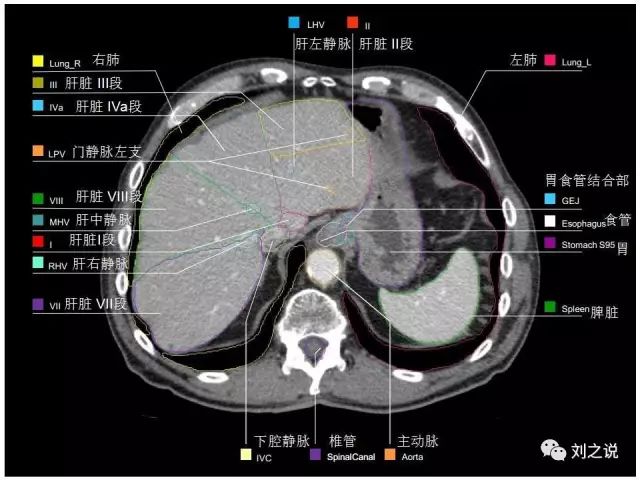

参考RTOG共识和3D-body解剖。

来源:刘之说